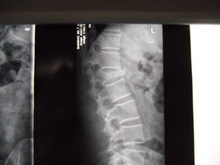

腰椎压缩性骨折

一、胸腰椎压缩骨折治疗组

本器材的原理:通过患者胸锁骨与耻骨联合处为支撑力点,用《可调式固定支具(腰椎型)》中提拉装置,提升腰部后面的固定带。把契形骨折通过腰部固定带直接提拉出正常范围内腰部的生理弧度。使胸腰椎契形状骨折,逐步改变弧度,从而使骨折部位复位。一般骨折二周内可以逐步通过提拉装置,每隔三天提拉一次,直至坐稳弧度在正常范围内为止。